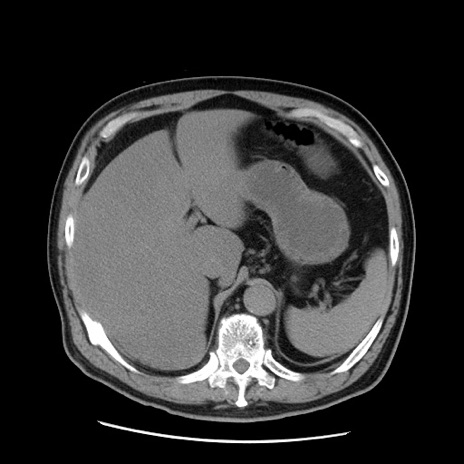

症例20(横断像)

【症例】 60歳代男性

【主訴】 腹部膨満、嘔吐

【現病歴】5日前頃より倦怠感を認め食事量減少し4日前の朝嘔吐、食事摂取困難となった。 3日前近医受診し点滴施行され整腸剤などを処方された。 当日他院を受診し、腹部膨満著明、炎症反応の上昇(CRP10.8、WBC11200)あり、紹介受診となる。

【身体所見】 意識JCS1 受け答えがはっきりしないBP 111/57mHg、 P 67bpm、、BT35.2°C、SpO2 97%(RA)、 腹部:膨隆、打診で鼓音あり、全体的に圧痛有り、腸蠕動音(-)、反跳痛ははっきりせず。

【データ】WBC 11400、CRP 14.20